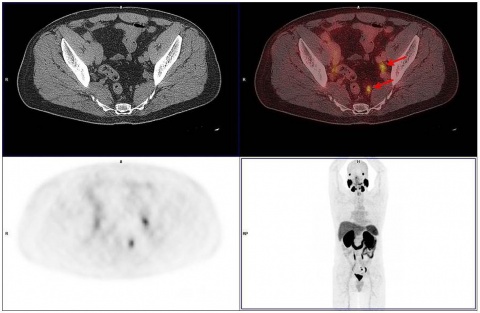

In der Abteilung Nuklearmedizin des BwZKrhs Koblenz wurden seit Juli 2015 insgesamt 193 Untersuchungen mit der PSMA PET/CT durchgeführt. Wir hatten die Gelegenheit in einer ersten Serie von Patienten nach Etablierung der PET/MRT im BwZKrhs Koblenz 34 Patienten, die eine PET/CT erhalten hatten, unmittelbar im Anschluss an diese einer PET/MRT-Untersuchung zuführen zu können (Abbildung 3).

Bei dieser (zunächst noch kleinen) Gruppe von Patienten fanden sich in 31 Fällen (31/34) Übereinstimmungen der Befunde. Keine einzige zusätzliche pathologische Veränderung (Läsion/Lymphknoten/Lokalrezidivsituation) wurde erst durch die zweite Untersuchung erkannt.

In drei Fällen (3/34) konnte eine Diskrepanz aufgezeigt werden; bei zwei Fällen war das PET/CT, in einem Fall das PET/MRT überlegen.

Bei einem Patienten waren drei im PET/CT hochstoffwechsel-aktive Prostatakarzinomherde im PET/MRT nicht abgrenzbar; der intraprostatische PET/MRT-Befund war nicht beurteilbar.

In einem zweiten Fall konnte ein kleiner, 9 x 8 mm messender Lymphknoten links infrapubisch mit deutlich gesteigerter PSMA–Avidität im PET/CT aufgrund des sogenannten „Halo-Artefaktes“ im PET/MRT nicht verifiziert werden. Der Lymphknoten wies einen erhöhten standardized uptake value (SUV) im PET/CT von 10,1 auf und war somit als eindeutig malignomsuspekt zu werten (Abbildung 4). Im MRT kam der Lymphknoten morphologisch als T2-hyperintens zur Darstellung, zeigte jedoch aufgrund eines ausgedehnten Halo-Effektes keine gesteigerte PSMA–Avidität im PET/MRT (Abbildung 5). In der Literatur wird der „Halo-Artefakt“ als typische Artefaktbildung im PET/MRT, die die Detektion von malignen Läsionen nahe der Harnblase bzw. der Nieren beeinträchtigt, beschrieben [3, 21].

Im dritten Fall wies das PET/MRT vier lymphogene Metastasen auf, während in der PET/CT lediglich zwei Lymphknotenfiliae eindeutig abgrenzbar waren.